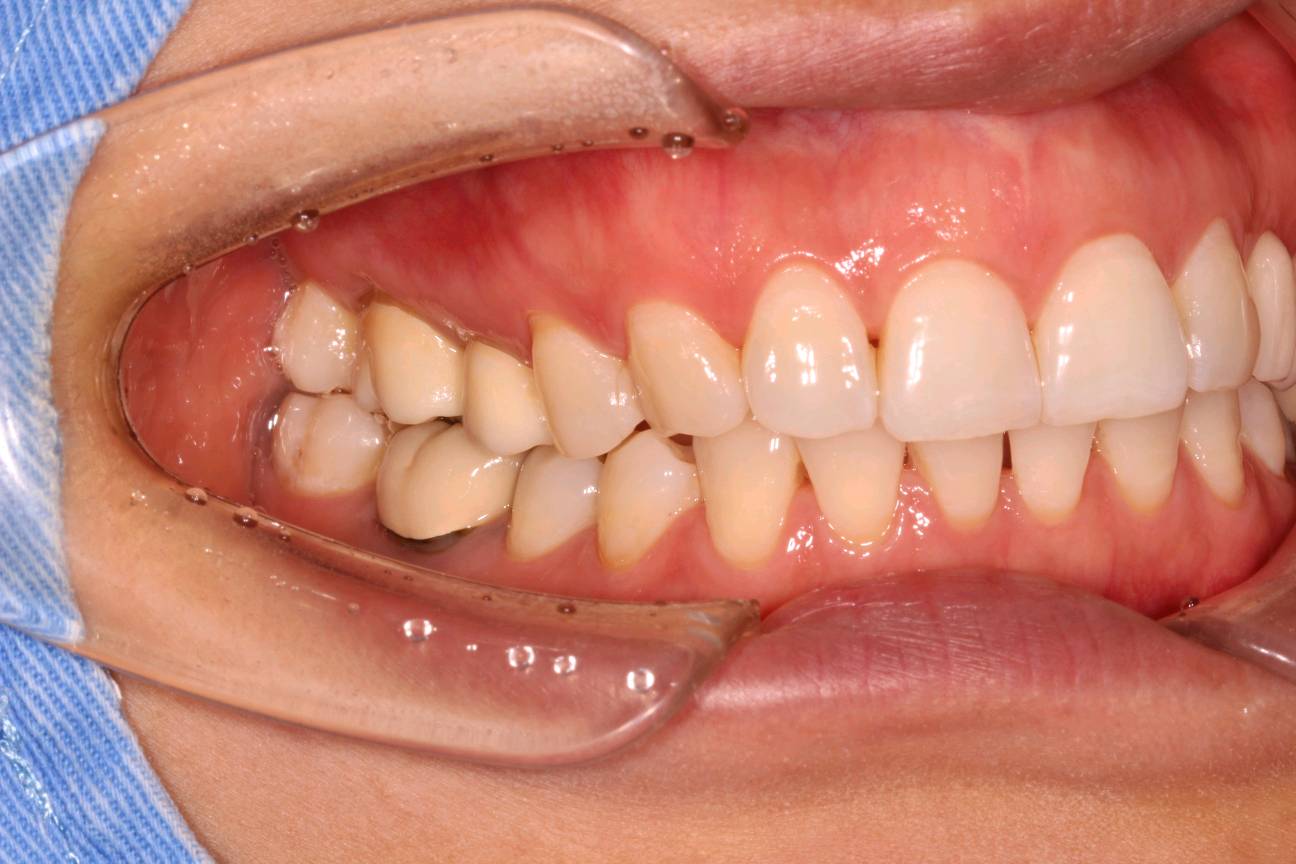

牙齿问题:患者之前在外院做的右下第一磨牙烤瓷牙冠,原烤瓷牙冠颜色苍白虚假,不美观,且金属内冠导致牙龈边缘开始发黑。

术前检查